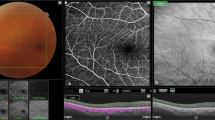

The imaging procedure is described in reference [10] and different imaging modalities and data analysis is illustrated in Fig. 1 for a patient with ODP and ODP-M. The patients were imaged with a scanning protocol taking 2.18 s, covering 45° while consisting of 1600 × 1600 A-scans. The resulting sampling density of 8.4 μm/A-scan compared to the transversal optical resolution of 21 μm corresponds to an oversampling by a factor of 2.8. In post processing, a moving average of 4 B-frames was computed from the multi-gigabyte datasets. The region of the optical nerve head (ONH) was selected and within this volume the inner limiting anatomical structures were detected. This was performed with customized software, whereas the segmentation was based on various parameters adjusted by a trained observer for the individual B-frames. Based on the temporal position of the RPE, the 3D-reconstructions were color coded in depth; volume and maximum depth was computed. The creation of a virtual 3D reconstruction including volume and depth measurement takes 1–4 h depending on the shape of the ONH and other pathologies. The accuracy of the algorithm is estimated to be ~50 μm for finding the inner limiting interface in a single A-scan.

Imaging modalities of the optic disc pit (ODP). a Fundus photograph of the left eye of an 18-year-old man (Pat. 1 in Table 1) showing a grayish temporal ODP with adjacent hyperpigmentation and visible zone-β with parapapillary atrophy of the RPE and choriocapillaris. Green arrow indicates OCT-level of 1E. b En face MHz-OCT image of the optic disc. The hatchy area infero-temporal suggests detachment of neuroretinal layers. c Infrared image of the optic disc and ODP. d OPTOS autofluorescence-image of the optic disc. e MHz-OCT scan of the ODP. The scanned en face levels in (1–3) are shown as labeled long green arrows in (e). e1 Orifice level of the optic disc’s NFL. Superficial retinal vessels are visible. e2 Choroidal level of the ODP. e3 Lamina cribrosa level showing the two peaked ODP as two rather ellipsoid dark holes that break through the lamina cribrosa. f / g Rotated virtual 3D volume of the ODP, illustrating the 3-dimensional structure of the optic disc

Covering up to 45 degrees field of view MHz-OCT generated a scan that allowed simultaneous evaluation of all ODP-associated pathologies within the optic disc as well as the macula region (Figs. 2 and 3). Different imaging modalities show different pathologic aspects in patients with ODPs (Fig. 1). On fundus photography classic congenital ODPs present mostly as grayish lesions within the surface of the optic disc, commonly located near the temporal margin of the optic disc [7, 20]. Especially in younger patients (Pat. 1, 18a; Pat. 2, 26a) with congenital ODPs, the MHz en face summation images showed very dark and circumscribable ODPs. En face MHz-OCT imaging is in this respect equal to Heidelberg infrared imaging of the optic disc that also presents the ODP as dark lesion in the optic disc surface. Especially in these two imaging modalities, horizontal ODP dimensions seemed more defined than in autofluorescence images. En face MHz-OCT proved itself as a means to depict the peripapillary choroid, with the deeper choroidal vessels forming a net around the optic disc (Fig. 1). ODP-M with retinoschisis, atrophy of inner retinal layers and serous macular detachment [2, 6, 7] can be visualized in top-view images by fundus photography, OPTOS imaging, autofluorescence and en face reconstructions. The area of retinal detachment can be seen on fundus photography, as well as on OPTOS pseudo-color images of the posterior pole. But the margin of the area of retinal detachment is better presented by autofluorescence and en face imaging. In these imaging modalities the margin of the detached retinal tissue is contrasting well with the non-detached areas (Fig. 2). In the MHz-OCT en face images the structure of the adjacent retina temporal to the ODP furthermore suggested retinoschisis with the ODP as source of the subretinal fluid. Conventional long horizontal MHz-OCT scans selected from the isotropic 1600 × 1600 A-scan dataset in post processing can show the course of the pit cavity along the outer border of the pre- and retrolaminar optic nerve and all characteristics of ODP-M, such as intra- and subretinal fluid, retinoschisis within ganglion cell layer, inner or outer nuclear layer and intrapapillary proliferations (Fig. 3).